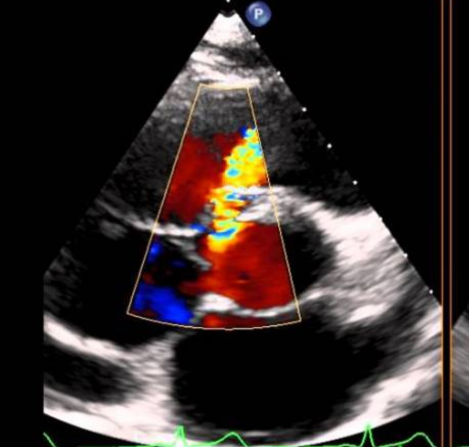

Ecocardiografías

La ecocardiografía emplea ondas sonoras para producir una imagen del corazón y ver cómo funciona. Según el tipo de estudio ecocardiográfico que se realice, puede determinarse el tamaño, la forma y el movimiento del músculo cardíaco. Este estudio también...